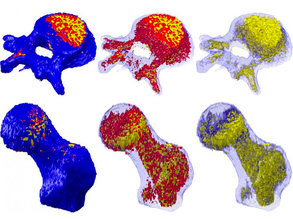

Bone Hard